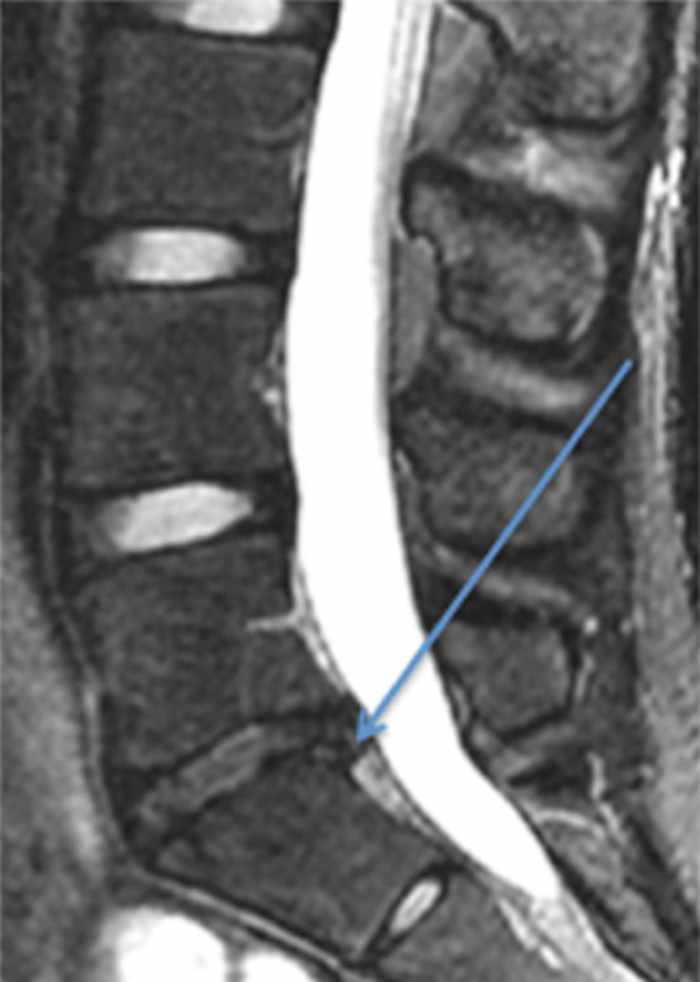

Another common injury to the low back of athletes is a herniated intervertebral disc. Professional athletes such as Tony Romo, Dwight Howard and Marian Hossa have all suffered this injury. The intervertebral discs are shock absorbers between the bones in the back. They are composed of a gel-like center portion (the nucleus pulposus) surrounded by a firm fibrous outer layer (the annulus fibrosis). If there is an injury to the outer fibrous layer, the inner portion can extrude out and compress local nerve roots (Figure 2). This often presents with pain shooting down a patient’s leg, and it may be associated with significant numbness, tingling and weakness in the leg.

Faced with these symptoms, athletes should immediately stop athletic activity and see a medical professional. Fortunately, these symptoms will often resolve in four to six weeks with rest and anti-inflammatory medications. However, if symptoms persist, surgical intervention can lead to a significant improvement in symptoms for most patients. Furthermore, surgical treatment for a herniated disc does not preclude patients from returning to sports, as over 80% of athletes who develop a herniated intervertebraldisc can return to sporting activity.